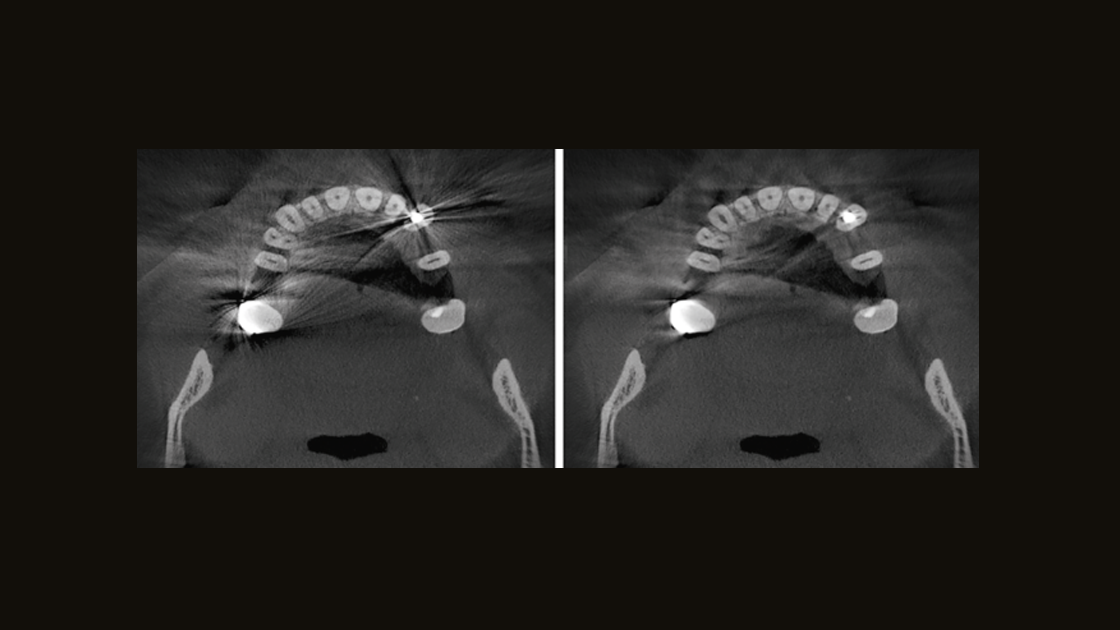

Mejore la salud bucal de sus pacientes al tener la capacidad de diagnosticar y planificar el tratamiento para casi todas las etiologías en la región dentomaxilofacial. Las soluciones en radiología de DS apoyan las necesidades del paciente, desde la captura de las articulaciones temporomandibulares hasta la visualización de los detalles más pequeños utilizando radiografías de endodoncia de alta resolución de hasta 80 µm.